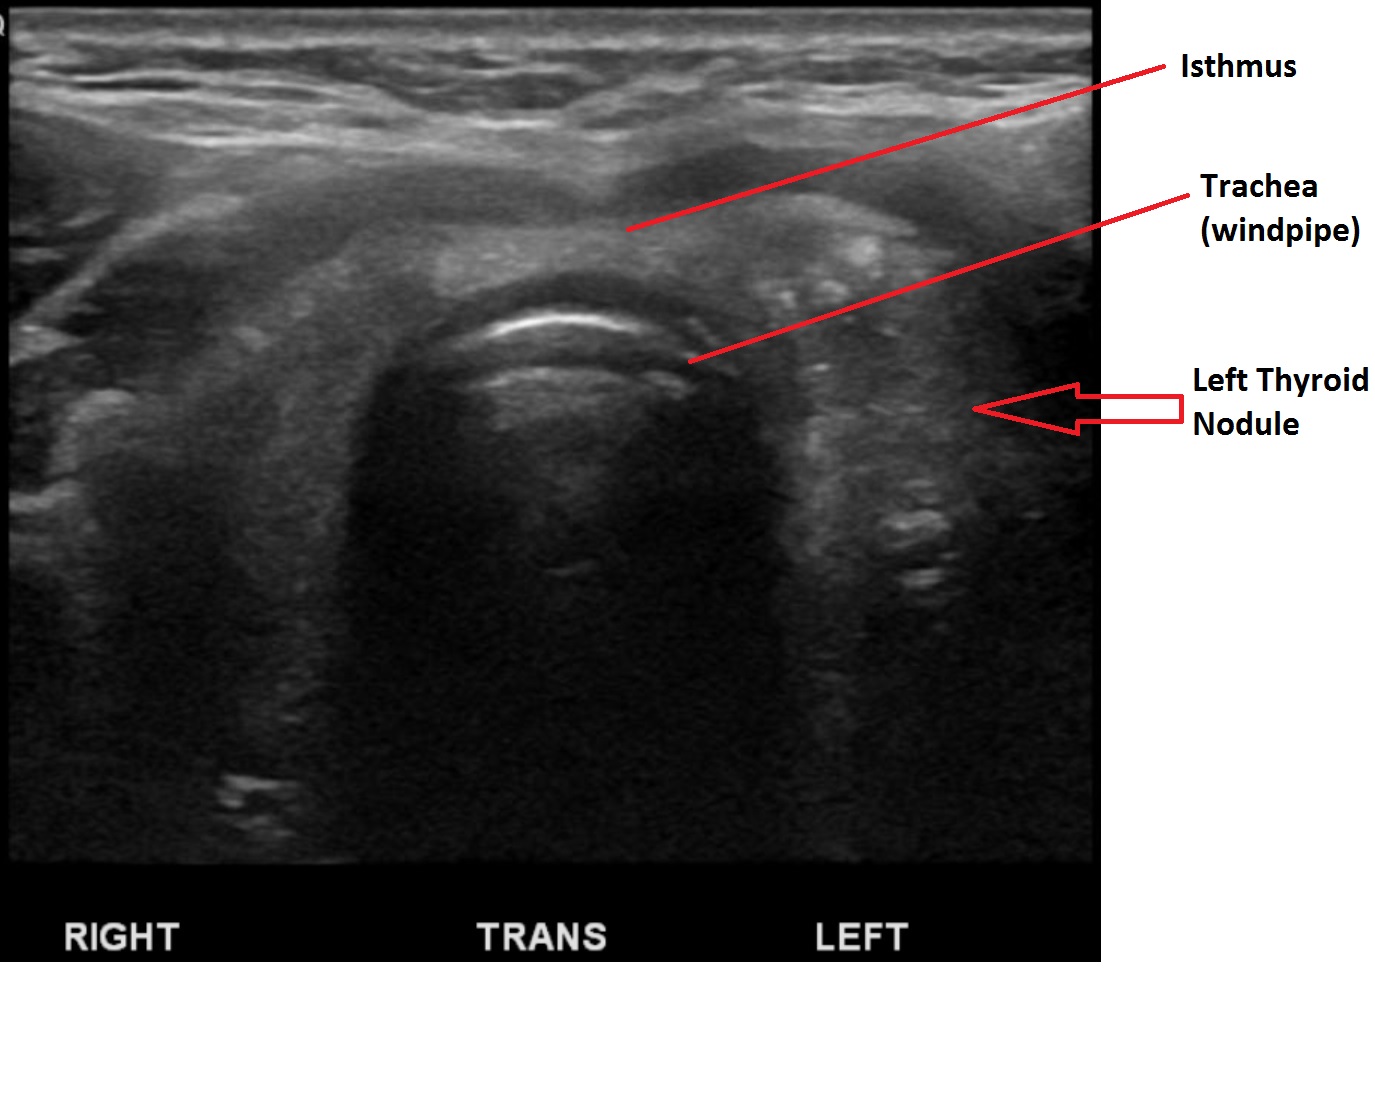

Thyroid ultrasound is the most common imaging modality performed in evaluating thyroid nodules. US imaging will provide information about the size of the thyroid, presence or abscence of nodules and may be used in evaluating lymph nodes in the neck. It will provide informatopn about the characteristics of thyroid nodules such as size, cystic vs. solid nature, echogenicity, shape, presence of calcifications, vascularity and location of the nodules. These characterisitcs will help the clinitian determine if further investigation such as biopsy is indicated.